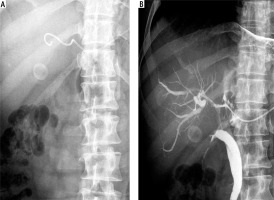

Fig. 2

Percutaneous transhepatic biliary drainage performed using a 5F catheter. A) 5F catheter introduced into the bile duct. B) Checking for catheter patency by injecting contrast through the catheter into bile ducts during follow-up cholangiography

PTBD was performed under ultrasound guidance with careful localization of the biliary tree and proper selection of the entry site. The procedure was performed using local anaesthesia. No conscious sedation was applied. The route for BD depended on the location and available ‘window’ for optimal access to the biliary tree. The access site (right or left lobe puncture) was chosen according to the pre-procedural imaging. Generally, the most commonly used method was the trocar technique using an 8F multisidehole catheter (Boston Scientific, Boston, USA), guiding it into the bile duct (Fig. 1). If the introduction of an 8F catheter into the bile duct was difficult or impossible due to the position or the diameter of the bile duct, a modified trocar method using a multisidehole 5F catheter (Boston Scientific, Boston, USA) was used instead. With this technique, a 14 gauge needle was first introduced into the bile duct. Subsequently, a 5 F catheter was introduced through the needle into the bile duct. After introducing the catheter and the establishment of BD through the catheter, the needle was removed (Fig. 2). The catheter was then secured to the skin and connected to a bag attached to the skin for continuous PTBD. In cases which required introduction of more than one catheter in order to improve BD, additional catheters were introduced by the same method in other selected bile ducts. If a catheter problem occurred, it was resolved by repositioning and flushing of the catheter or by introducing a new one.

The number and size of the catheters were determined individually for each patient by the clinicians and interventional ultrasonographists. Their decisions were based upon clinical considerations, the size and location of the bile duct and its relationship to the surrounding vascular structures. Colour Doppler sonography was performed prior to intervention in order to determine the catheter pathway through the liver tissue towards the targeted bile duct, avoiding vascular structure damage. In general, colour Doppler sonography was not used during the intervention as it was more difficult to follow the catheter tip passing through the liver tissue. Adequate drainage is usually confirmed by a steady decline in serum bilirubin concentrations. Catheter patency was checked by injecting contrast and observing its passage through the catheter (Figs. 1, 2).